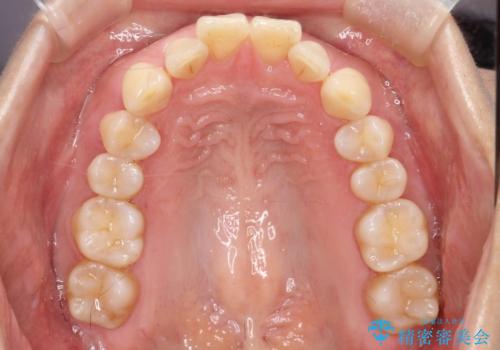

- 前歯が出ていることを主訴に来院されました。

インビザラインにて臼歯部の遠心移動及びIPRを行なっています。

叢生量が多いケースでしたが、綺麗な歯並びとなり患者様にも満足していただきました。